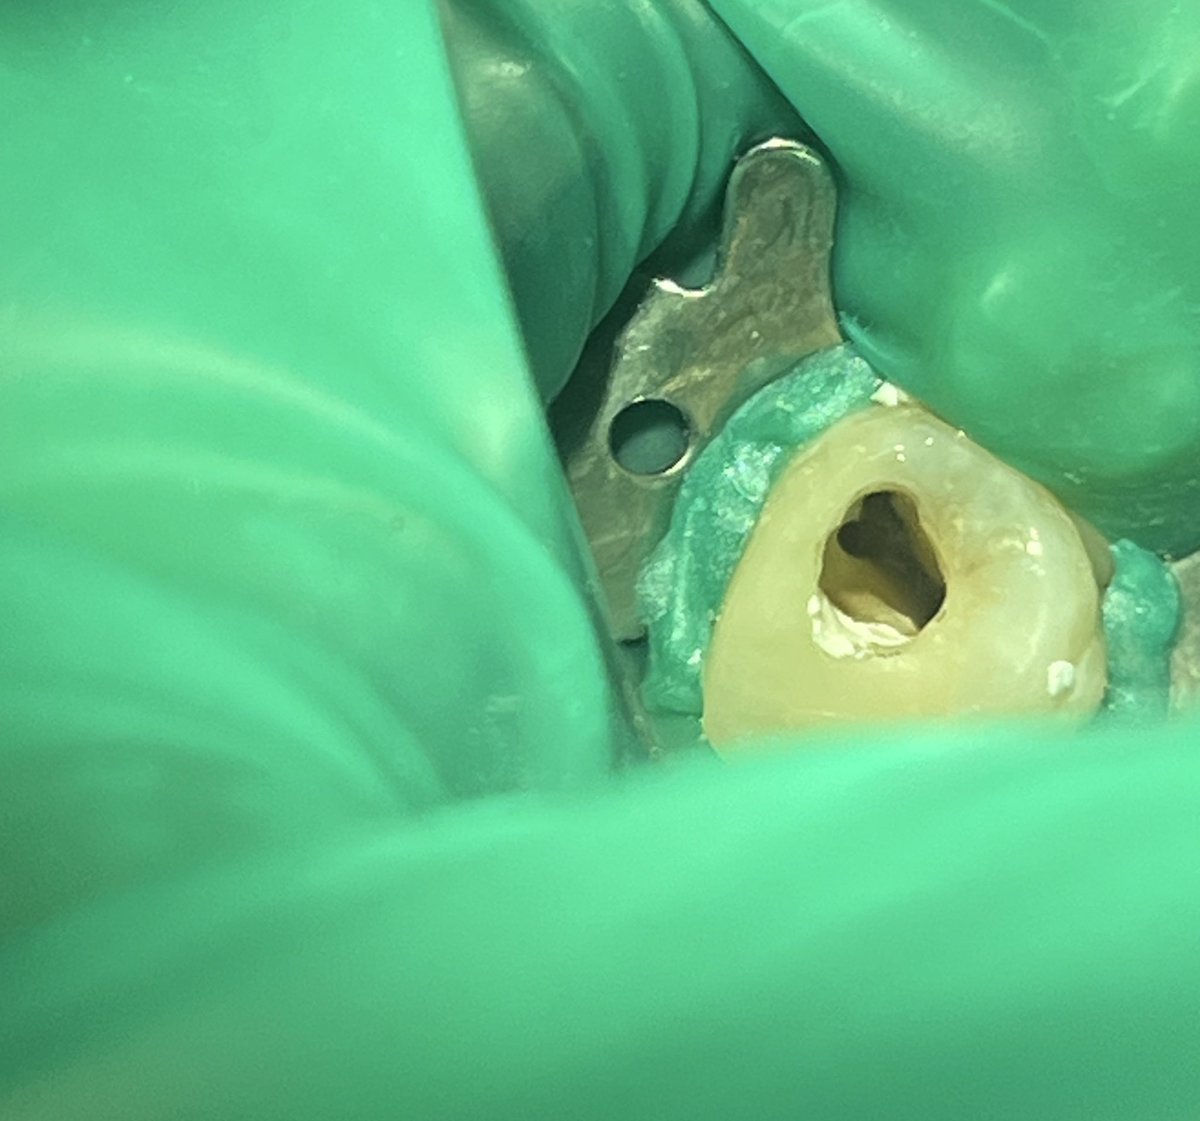

حالة جميلة لصباح اليوم 🙏🏻

Root Canal Treatment #34

Dx:SIP+SAP

Gingival overgrowth and deep caries in the distal wall, Rebuild the distal wall to achieve optimum isolation ✨

Next Step: Crown